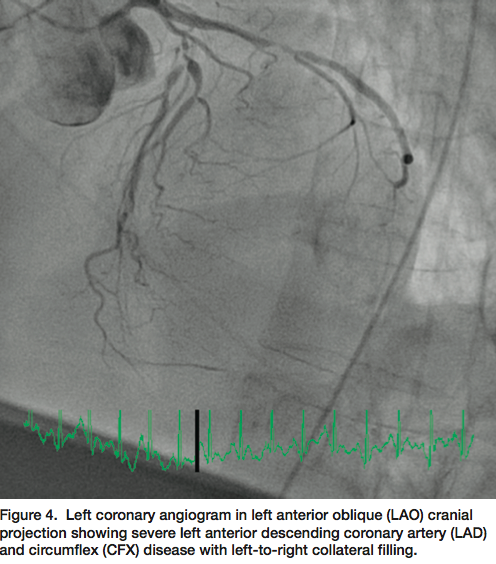

Little did I anticipate that this patient would have the worst peripheral vascular and coronary artery disease I had seen in ten years. The procedure began from the femoral approach since she had bilateral wrist contractures and no pulses. Ultrasound-guided femoral artery access was used since there were no palpable femoral pulses. After an hour of attempts for access, we found that the right iliac artery was 100% occluded and the left femoral and iliac arteries were diffusely diseased, with serial 90% lesions to the aortic junction (Figures 2-3). We were able to pass 5 French catheters to the coronary ostia and found that both the left and right

coronary arteries were severely and diffusely diseased, with multiple and serial critical lesions throughout (Figures 4-6). The left ventricular end diastolic pressure was 35 mm Hg and ventriculography was deferred. Based on the terrible state of all coronary arteries, the severely impaired left ventricle, and her underlying condition, I felt that PCI was futile. We concluded our procedure at 3am and transferred the patient to the recovery room. She felt she did not want to continue using the supplemental oxygen mask that was needed to maintain her oxygen saturations. She requested we remove the mask and two hours later she succumbed.